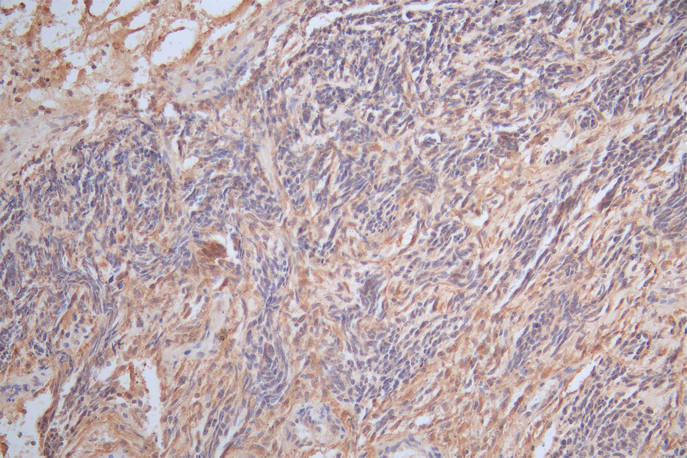

IHC image of GFAP Recombinant Monoclonal Antibody diluted at 1:300 and staining in paraffin-embedded human glioma cancer performed on a Leica BondTM system. After dewaxing and hydration, antigen retrieval was mediated by high pressure in a citrate buffer (pH 6.0). Section was blocked with 10% normal goat serum 30min at RT. Then primary antibody (1% BSA) was incubated at 4°C overnight. The primary is detected by a Goat anti-Mouse IgG labeled by HRP and visualized using 0.05% DAB.